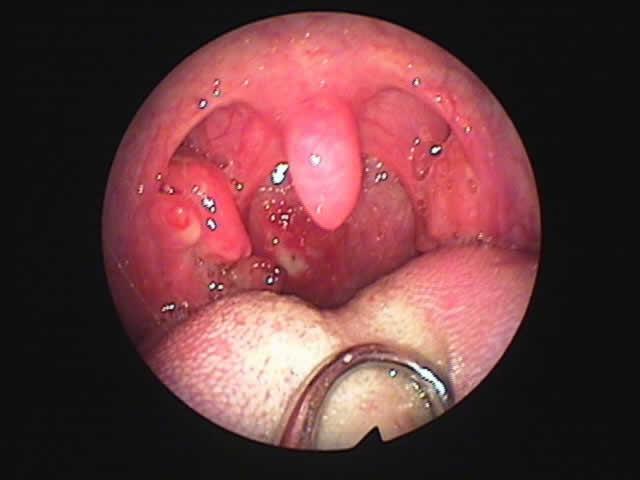

| 左扁桃術直後(31歳男性,6月9日) 数カ所針電極を刺入 | 白い部分が変性部位(6月11日) | 右扁桃術直後(7月7日) |

| 7月16日 かなり縮小 | 両手術直後(縮小不十分なため追加焼灼、8月9日) | 9月8日 著明に縮小しいびき消失しているとのことです |